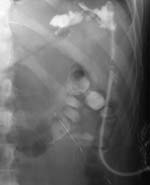

1. Сочетание фистулографии урографином с пневмоколоноскопией (раздувание толстой

кишки воздухом) у больного Я., 25 лет, находившегося на стационарном лечении

в хирургии с длительно незаживающим свищом после пулевого ранения брюшной полости,

позволило диагностировать перфорацию нисходящего отдела ободочной кишки, поддерживающую

гнойно-воспалительный процесс в брюшной полости. Точная локализация перфоративного

отверстия (места, где контраст через свищевой ход попал в просвет толстой кишки

на фоне ее раздувания воздухом) позволило квалифицированно устранить причину

нагноительного процесса и обеспечить выздоровление пациента (Рис. 1).

Рис. 1. По дренажной трубке в свищевой ход введено контрастное

вещество (Слева). В толстую кишку (per rectum) введен воздух

(Справа). В просвете толстой кишки определяется контраст,

что свидетельствует о наличии толстокишечного свища.